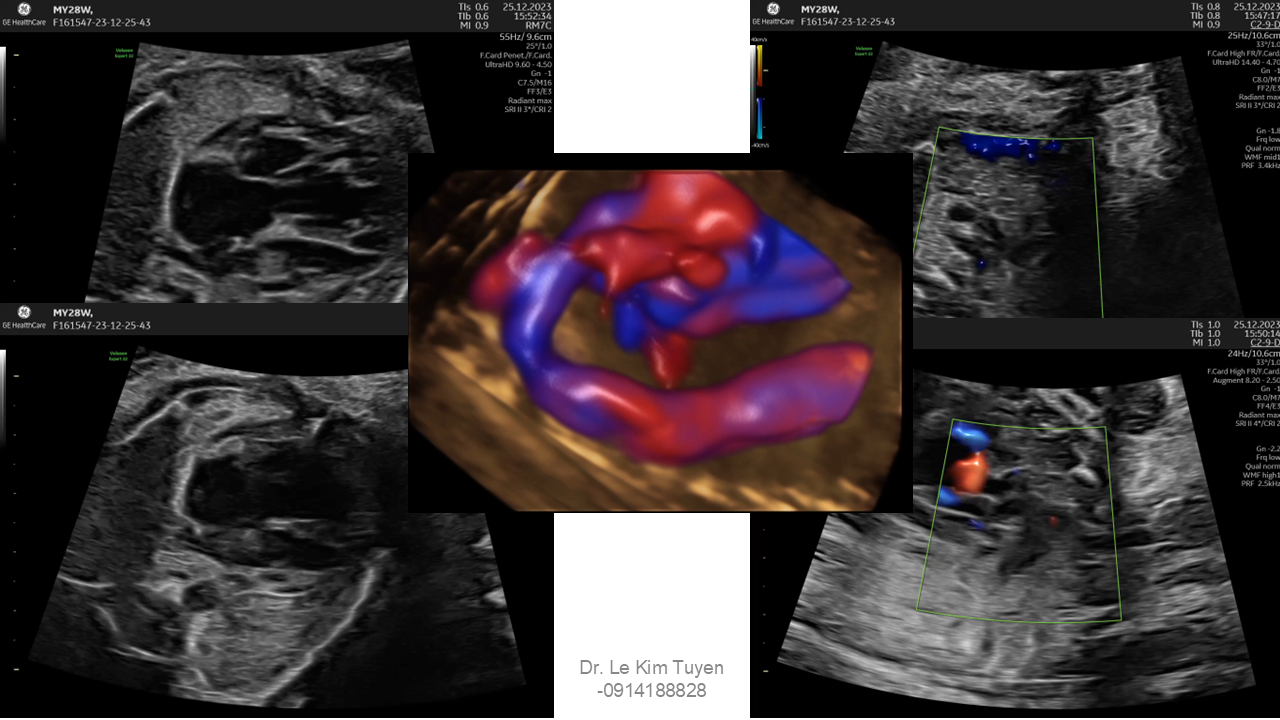

Áp dụng công nghệ Graphicflow trong phát hiện bệnh tim bẩm sinh cần cấp cứu sơ sinh

TS. BS. Lê Kim Tuyến

Bệnh viện Tim Tâm Đức